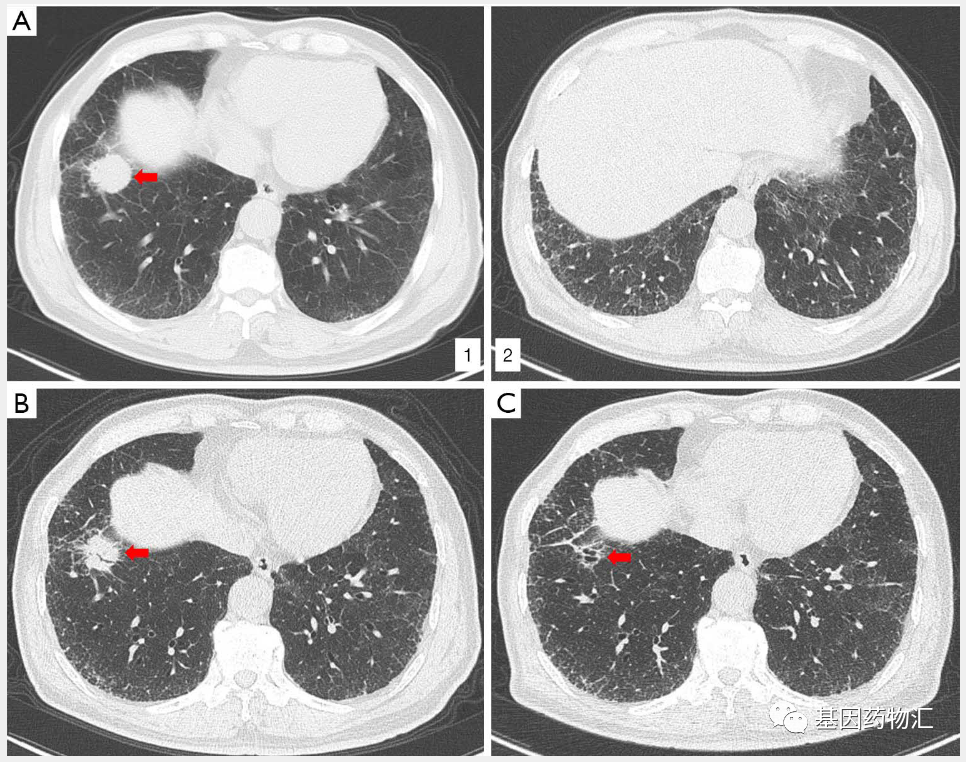

(A1)确诊时原发病灶;(A2)双侧肺间质性肺病;(B)治疗2个周期后,原发病灶缩小;(C)治疗4个周期后,原发病灶已经消失。

从2018年1月开始,治疗4个周期后,患者达到了部分缓解;治疗6个周期后,患者达到了完全缓解!至2年后,2020年3月复查时,患者仍然保持着完全缓解。